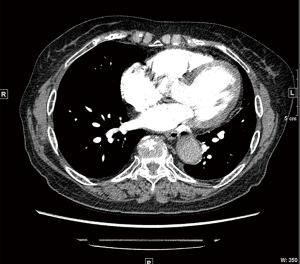

Next, the abdominal CT revealed that the transverse colon and colonic hepatic curvature were thickened and densified, the serous membrane surface was rough, and the fat exudation had improved. Subsequently, pulmonary artery computed tomography angiography (CTA) was performed, which suggested (Figure 4) multiple filling defects at the distal end of the right pulmonary artery, the distal end of the right upper pulmonary artery, the proximal end of each segment of the arteries, the dorsal segment of the right lower lung, the proximal branch of the basal segment of the artery, and the distal end of the left lower lobe of the basal segment. Thus, a diagnosis of pulmonary embolism was considered. Additionally, the thrombotic thrombocytopenic purpura (TTP) test results were negative.